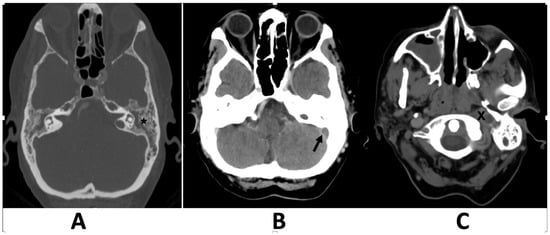

A 74-year-old woman visited the emergency department because of symptoms that had persisted for several weeks. These symptoms include ear pain, hoarseness, difficulty swallowing (dysphagia), dizziness, ear ringing (tinnitus), and hearing loss. Physical examination revealed a reddish bulging of the tympanic membrane. Left-sided hearing loss and right uvula deviation from the left palate paresis were also observed. The findings of the head impulse test were indicative of a positive result on the left side, whereas the examination of spontaneous horizontal nystagmus revealed its presence on the right side. Neurological examination revealed cranial nerve palsies affecting the ninth and tenth cranial nerves, respectively. Nasopharyngeal endoscopy revealed adenoid tissue that was not suspected. The blood cell counts revealed moderate neutrophilic granulocytosis and an elevated C-reactive protein level. Bacterial cultures from the ear discharge were positive for Fusobacterium necrophorum. High-resolution computed tomography (CT) of the left ear revealed coalescent mastoiditis and complete middle ear opacification without erosion of the mastoid septa (Figure 1).

Figure 1. Computed tomography scans axial plane, obtained with and without contrast media administration at the level of the mastoid (A), showing complete opacification of the middle ear and mastoid without mastoid septal erosion (asterisk), and at the level of the sigmoid sinus showing a thrombotic lateral sinus (B), and the left jugular vein (C). A filling defect in the left sigmoid sinus (arrow) and jugular bulb (X), indicating acute thrombosis, is evident.